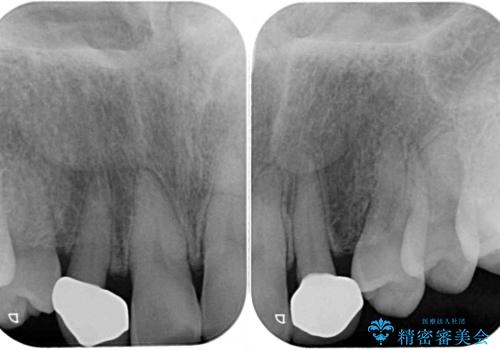

上顎の矮小歯は隙間が多く、歯軸の傾斜も大きかったため、部分矯正により補綴治療前に歯の位置を整えることとしました。

下顎の乳歯は支台歯として機能することは困難と思われたので、事前に抜歯をし、上顎の矯正治療終了のタイミングに合わせて、セラミックブリッジにて補綴治療することとしました。

前歯部はディープバイトという、上顎前歯が下顎前歯に深く覆い被さる咬合であったので、理想的には全顎矯正が必要となりますが、今回は患者希望により前歯部のみの部分矯正で対応しました。そのため下顎犬歯の神経を取り除くことになってしまったのは心残りであります。